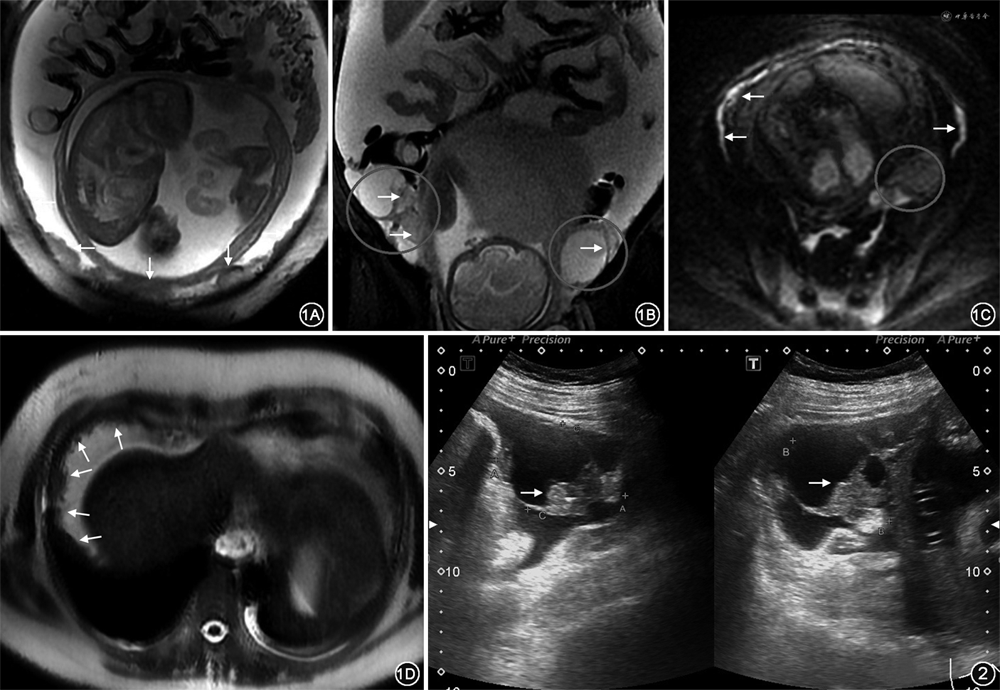

孕妇37岁,孕2产1,因“停经29周+4,发现盆腔包块1个月余,下腹胀6 d”于2020年11月22日入院。患者于1个月余前外院超声检查提示,左侧附件区2.8 cm×3.4 cm×2.5 cm囊性包块;6 d前自觉下腹胀,外院超声检查提示,左侧附件区6.2 cm×5.3 cm×4.1 cm囊实性包块,盆腹腔大量积液;血清CA125水平为2 473.2 kU/L(正常值:<35 kU/L)。入院后血清CA125水平为1 444.0 kU/L,人附睾蛋白4(human epididymis protein 4,HE4)水平为2 056.0 pmol/L(正常范围:33.0~88.7 pmol/L)。腹水脱落细胞学检查提示,镜下见成团腺癌细胞。胸部CT平扫未见异常。腹部MRI平扫,肝包膜下、肝肾、脾肾隐窝及腹壁见结节灶,腹膜、大网膜增厚,盆腹腔大量积液,后腹膜淋巴结肿大,双侧附件区占位病变。见图1。考虑恶性肿瘤伴种植。超声检查提示,右侧附件6.7 cm×6.2 cm×4.6 cm囊性包块,左侧附件5.8 cm×6.0 cm×4.2 cm囊性包块,囊壁两处偏强回声。见图2。查体:生命体征平稳,心肺无异常,腹膨隆,移动性浊音无法叩诊。产科检查:宫高32 cm,腹围112 cm,估计胎儿体重1 400 g。三合诊:因腹膨隆子宫及双侧附件区触诊不满意,肛查可触及直径约5 cm包块,向直肠前壁压迫,活动性差,直肠黏膜光滑完整。